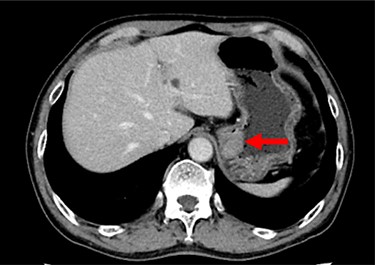

A 74-year-old man presented to the hospital for follow-up esophagogastroduodenoscopy (EGD) after Helicobacter pylori eradication. EGD revealed a large necrotic ulcerated mass at the cardia of the stomach (Fig. 1). Endoscopic biopsy revealed a malignant tumor negative for cytokeratin AE1/AE3, CD45, chromogranin A and synaptophysin on immunohistochemical (IHC) staining, and initial diagnosis was poorly differentiated adenocarcinoma. Physical examination, routine blood investigations and serum tumor marker levels, including carcinoembryonic antigen, CA-125 and CA 19-9, were normal. Abdominal computed tomography (CT) showed thickness of the stomach wall directly below the esophagus (Fig. 2, red arrow). Enlarged lymph nodes and distant metastatic lesions were absent. Radical surgery including total gastrectomy and D2 lymph node dissection was performed. Surgical specimens demonstrated a whitish amelanotic mass with central ulceration, present at EGJ, measuring 38 mm × 30 mm and protruding into the gastric lumen (Fig. 3A). Histological examination revealed polygonal and round neoplastic cells with round nuclei and prominent nucleoli nestled within the esophageal squamous epithelium, thus forming an ‘in situ’ lesion. No melanin deposition was found in the neoplastic cells. Immunohistochemically, neoplastic cells were positive for HMB45 and S-100 (melanoma markers; Fig. 3B–D). The final diagnosis was primary amelanotic malignant melanoma of esophagus, T2, N0 and M0 (UICC [International Union against Cancer] classification system, 7th ed.). Four months after surgery, abdominal CT revealed multiple liver metastases. The patient received seven cycles of nivolumab monotherapy, with two subsequent cycles of nivolumab and ipilimumab. Liver metastases were initially controlled by immunotherapy, but they eventually worsened, as assessed by the Response Evaluation Criteria in Solid Tumors ver. 1.1 (Fig. 4).

Contrast-enhanced CT showing the thickness of the gastric wall in the upper stomach (red arrow).